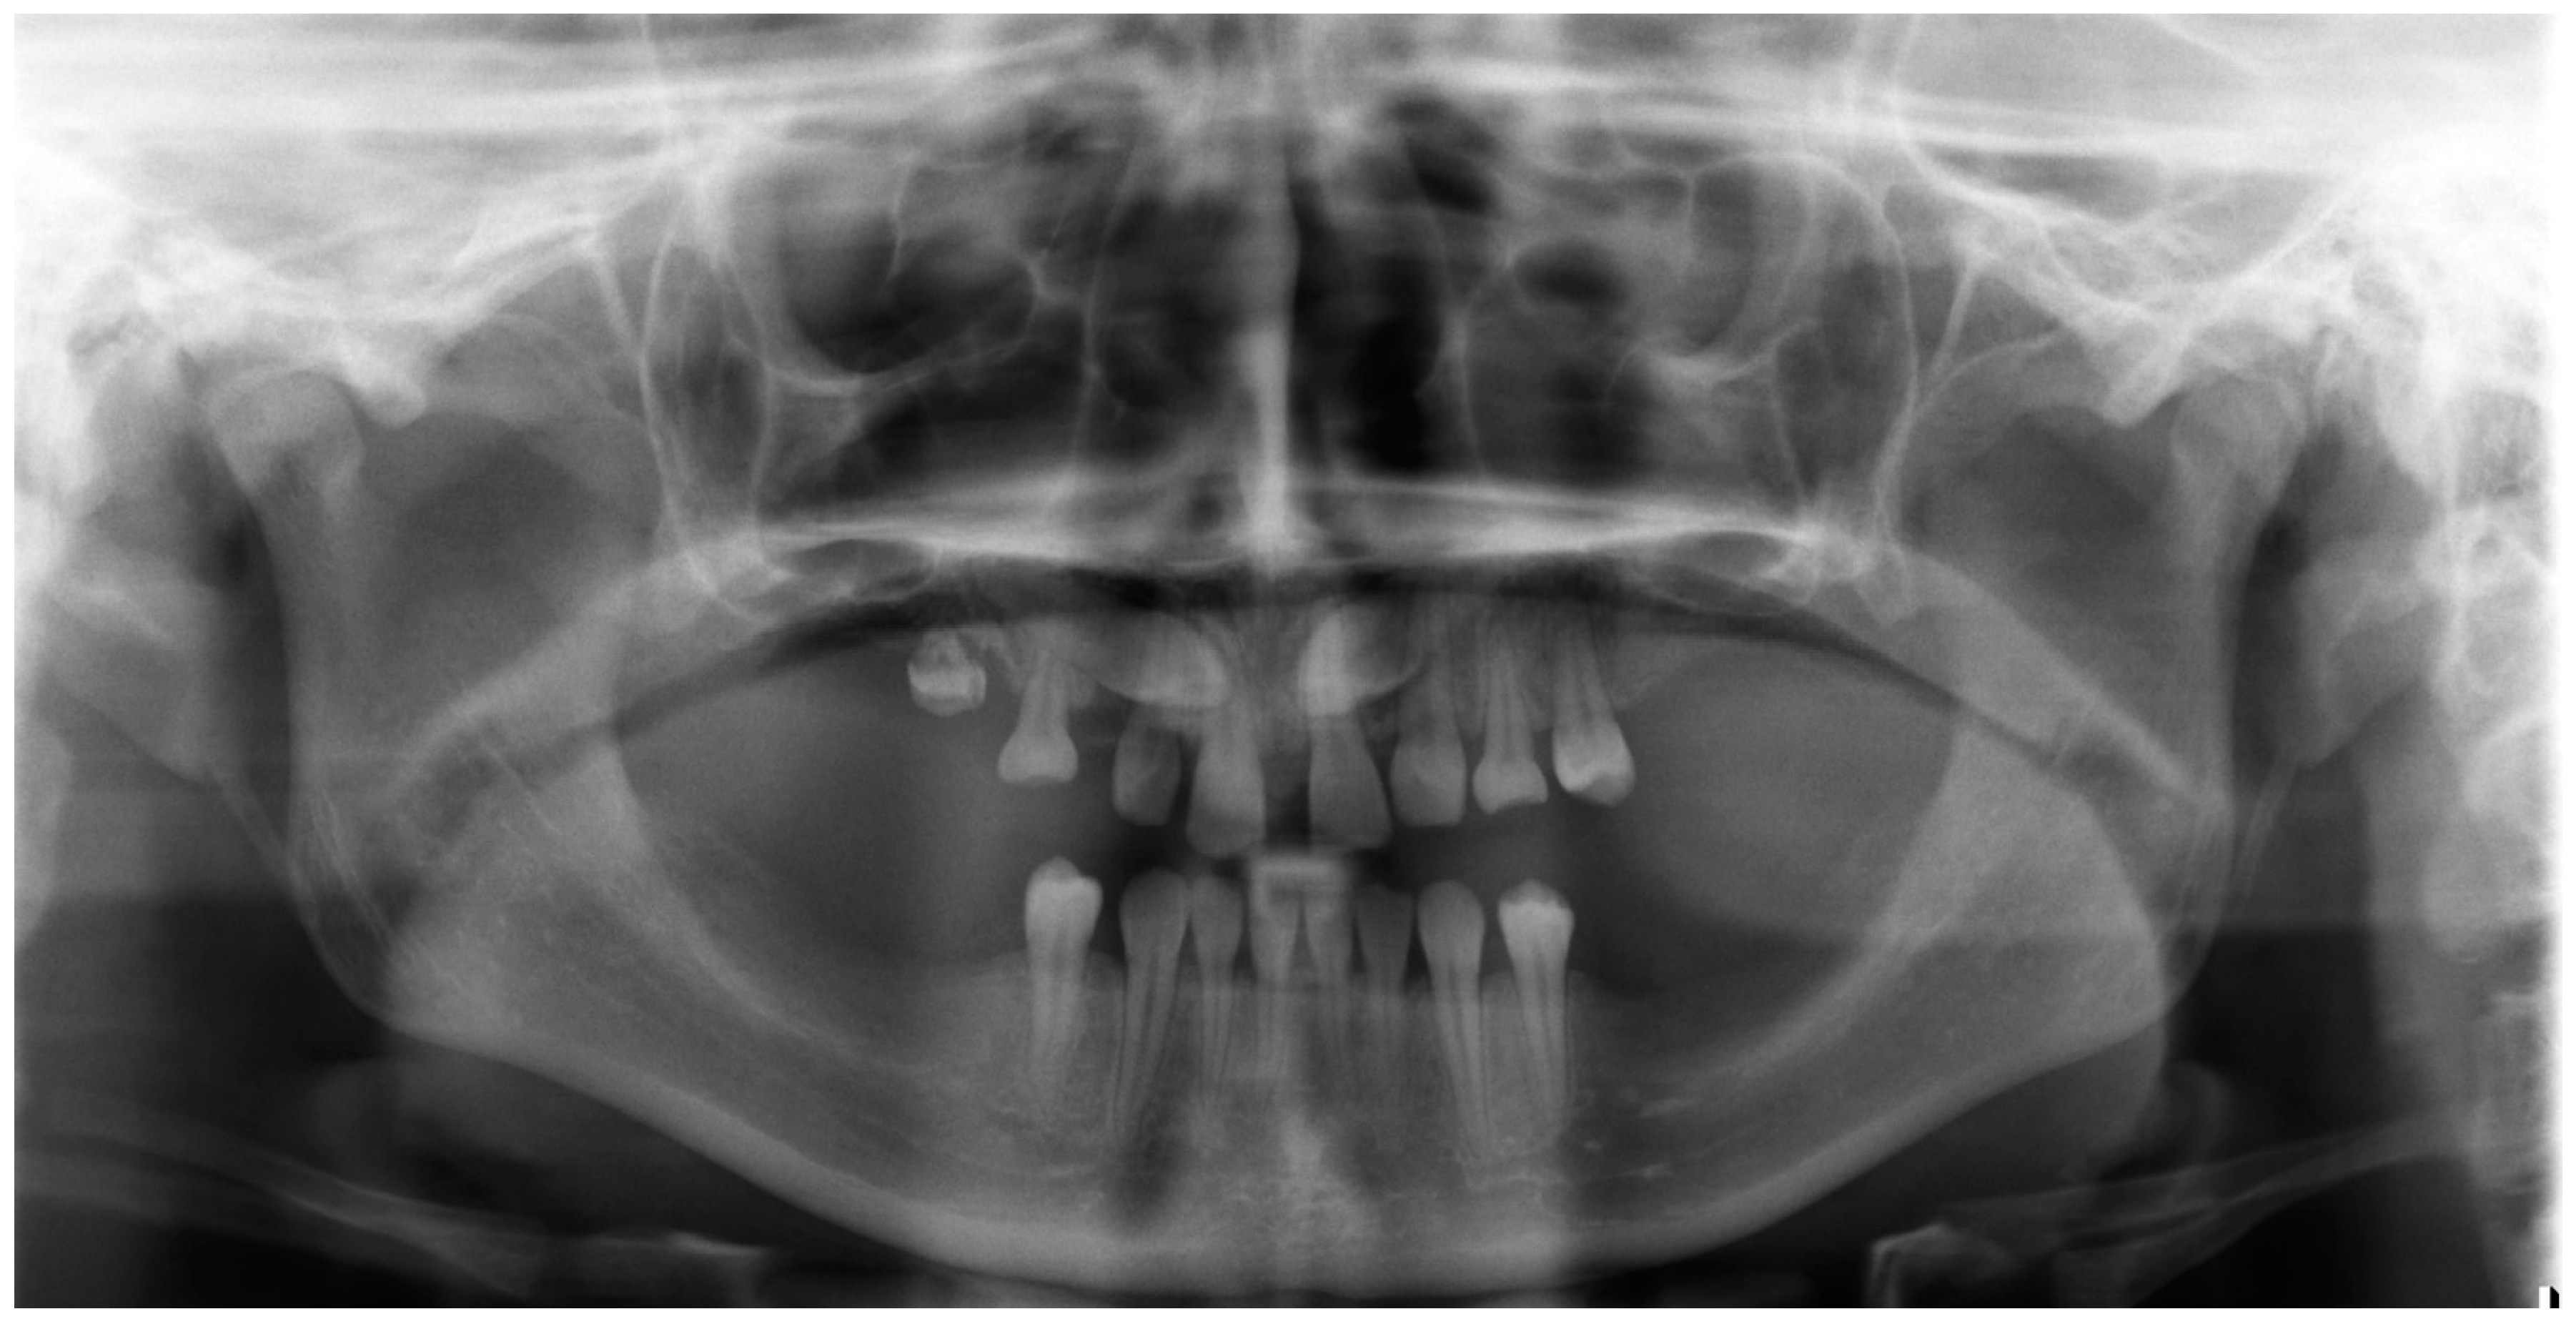

| October 2017 | PDCs’ surgical exposure—open technique; brackets bonded on PDCs; MIs tomas®-pin SD 06 (Dentaurum, Ispringen, Germany) inserted in the palatal alveolar region; 0.016″ × 0.022″ TMA cantilevers activated in distal and downward direction (50 g) (Figure 6a,b). |

| November 2017 | Visible orthodontic movement—exclusion of primary ankylosis (Figure 6c). |

| December 2017 | Increased mobility and tenderness of PDCs, dismantlement of cantilevers, button on the buccal side of UL3 (derotation), power chains to move the teeth (Figure 6d). |

| January 2018 | Teeth stability improved; 0.017″ × 0.025″ TMA cantilever with activation in downward and buccal directions for UR3, power chain for distal movement and derotation of UL3. |

| February 2018 | Button on the buccal side of UR3 (derotation), power chains for distal movements and derotations (Figure 6e). |

| April 2018 | Extraction of the upper right deciduous canine due to the collision with movement of UR3; 0.017″ × 0.025″ TMA cantilever activated for buccal movement of UR3 (50 g) (Figure 6f). |

| June 2018 | Partial fixed upper SS appliance Equilibrium® 2 0.022″ in Roth prescription (Dentaurum, Ispringen, Germany), 0.016″ NiTi wire, continuous metal ligature to create space for UL3; cantilever activation (Figure 6g). |

| August 2018 | Bracket on tooth no. 24; 0.016″ NiTi wire and open coil spring to create space for UL3; extraction of the upper left deciduous canine. |

| October 2018 | New MI tomas®-pin SD 08 (Dentaurum, Ispringen, Germany) was inserted in the buccal surface of left alveolar ridge; 0.017″ × 0.025″ TMA cantilever for buccal movement of UL3 (50 g) (Figure 6h). |

| November 2018 | Mobility of the buccal alveolar MI, the miniscrew was tightened and left to stabilize for a month; tooth no. 55 was extracted due to progressive reinclusion. |

| December 2018 | Buccal alveolar MI was lost and new MI tomas®-pin SD 10 (Dentaurum, Ispringen, Germany) was placed in the IZC; 0.017″ × 0.025″ TMA cantilever with buccal activation for UL3 (50 g). |

| February 2019 | Inflammation and submucous abscess in the IZC; MI removal; antibiotic. |

| April 2019 | New MI tomas®-pin SD 10 (Dentaurum, Ispringen, Germany) was inserted in the palatal suture and used as a direct anchorage with 0.017″ × 0.025″ SS cantilever and power chain for buccal movement of UL3 (50 g); 0.016” SS wire and bend-out for UR3 (Figure 6i). |

| May 2019 | Overcorrection of UR3 transversal relationship, 0.018″ SS wire and bend-out for tooth no. 22, new power chain from cantilever to UL3 for its buccal movement. |

| July 2019 | Tooth no. 22 in correct sagittal relationship; MI in the palatal suture used as an indirect anchorage: 0.017″ × 0.025 SS connection wire with tooth no. 24, 0.017″ × 0.025″ cantilever with buccal activation for UL3 (50g); 0.017″ × 0.025″ Cooper NiTi wire (Figure 6j,k). |

| March 2020 | The correct position of UL3; tooth no. 24 showed significant mobility; control panoramic X-ray: root resorption of tooth no. 24 (Figure 7); no possibility to conduct control visits on a regular basis due to COVID-19 pandemic—next appointment took place in November 2020. |

| November 2020 | 0.019″ × 0.025″ SS wire, torque expression, closure of spaces with power chain. |

| March 2021 | Removal of MIs, 0.021″ × 0.025″ TMA wire for torque expression in the upper arch; Fixed lower SS appliance Dentaurum Equilibrium® 2 0.022″ in Roth prescription (Dentaurum, Ispringen, Germany); 0.016″ NiTi wire; elastics 4 ½ oz. from palatal buttons on teeth no. 12 and 22 to the lower arch to correct the anterior crossbite (Figure 6l). |

| April–June 2021 | Further alignment of the lower teeth by means 0.017″ × 0.025″ NiTi, and next 0.019″ × 0.025″ SS; intermaxillary elastics 4 ½ oz and offset bends on teeth no. 12 and 22 were used to correct the anterior crossbite; elastic power chains for space closure. |

| August 2021 | Open sinus lift surgery with porcine bone-derived grafting material (The Graft™ bone substitute cancellous granules (Purgo Biologics, Seongnam, Republic of Korea) and BioCover™ resorbable collagen membrane (Purgo Biologics, Seongnam, Republic of Korea)) was performed on the right side of the maxilla. |

| March 2022 | Two dental implants were placed: tooth no. 14—Axiom® PX 3.4 × 12 mm (Anthogyr, Sallanches, France), tooth no. 15—Axiom® PX 3.4 × 10 mm (Anthogyr, Sallanches, France). |

| May–August 2022 | Finishing; control panoramic X-ray (Figure 8); 1st canine relationships and midline consistency; debonding of the brackets; fixed upper and lower retainers’ placement (0.027″ × 0.011″ 8-strand braided SS), tooth no. 24 was not fixed to the retainer due to increased mobility. |

| September 2022 | E-max (lithium desilicated ceramic) veneers on upper teeth; individual implant abutments (titanium pre-milled abutments) and implant-supported blocked crowns (zirconia veneered with porcelain using the cut-back technique) on dental implants; removable thermoformable retainer. |

| March 2023 | Retention phase: 10-month follow-up. Stability of treatment results; minimal opening of the spaces mesially to teeth no. 34 and 44; proper mobility of tooth no. 24. Bleaching of the lower teeth. |